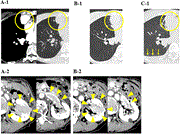

Massive gastric distension due to bulimia nervosa: a hotpot emergency

Jordan D Lee and others

Journal of Surgical Case Reports, Volume 2022, Issue 8, August 2022, rjac193, https://doi.org/10.1093/jscr/rjac193